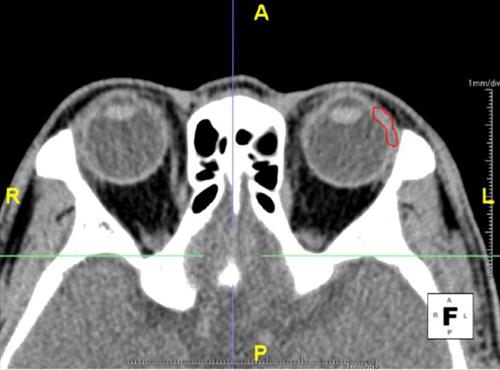

| △ 전산화 단층촬영으로 본 눈물샘의 모습. 빨간색 부분이 눈물샘이다. |

연구팀은 얼굴 단층촬영을 통해 눈물샘 및 안와(눈을 둘러싸고 있는 뼈)에 특이 질환이 없는 109명(213안)을 대상으로 연령에 따른 눈물샘 부피 변화를 분석했다. 조사 대상의 평균연령은 43.5세(20~78세)로 남성 54명, 여성 55명이었다.

이 결과 한국인의 눈물샘 평균 부피는 오른쪽 눈 0.589㎤, 왼쪽 눈 0.583㎤로 각각 조사됐다.

연령대별 눈물샘의 평균 부피는 20~40세 0.630㎤, 41~60세 0.553㎤, 61세 이상 0.544㎤로 연령이 증가할수록 눈물샘의 부피가 감소했다.

또 이런 현상은 남녀 모두에서 같았는데, 연령 증가에 따른 절댓값의 차이는 남성(0.644→0.548→0.572)보다 여성(0.616→0.559→0.518㎤)이 더 컸다.